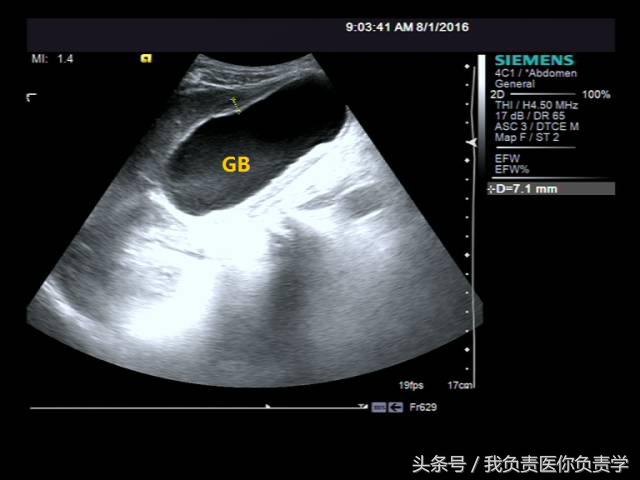

患者男,64岁,因右上腹疼痛半月余就诊。查体发现右上腹部轻压痛,无发热。超声检查所见如下:

图1示胆囊增大,囊壁增厚,囊内透声差